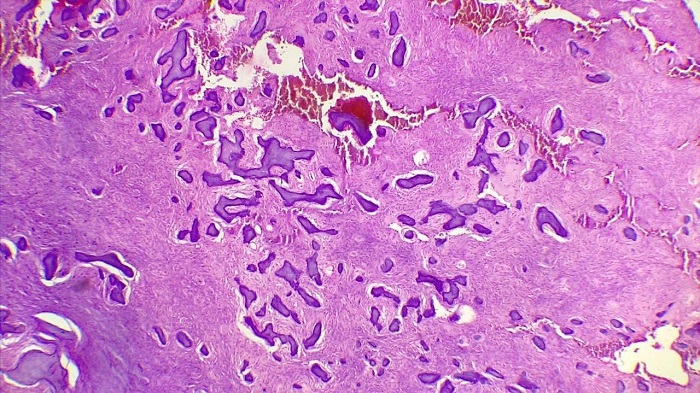

Previo a la realización del tratamiento, se obtuvo el consentimiento informado del paciente y se realizó una biopsia incisional de la lesión. El estudio histopatológico identificó una lesión tumoral fusocelular y tejido conectivo denso con un patrón esteriforme que rodeaba trabéculas óseas con una palizada de osteoblastos, con calcificaciones y tejido osteoide, moderadamente celular y sin clara atipia. La lesión estaba acompañada de células gigantes y áreas de hemorragia que sugerían un FO de la variante juvenil (figura 4).

Se decidió eliminar la lesión, extraer los dientes comprometidos (segundo premolar y primer molar inferiores izquierdos) y efectuar remodelado. Para comprobar la exéresis total de la lesión (figura 5) se tomó una radiografía y se envió nuevamente a análisis de patología, cuyos cortes mostraron una lesión fibrósea benigna constituida por numerosas trabéculas óseas curvilíneas, con apariencia de “letras chinas”, sin recubrimiento osteoblástico e inmersas en un estroma de tejido fibroso moderadamente celular, sin atipias. El diagnóstico fue DF (figura 6).